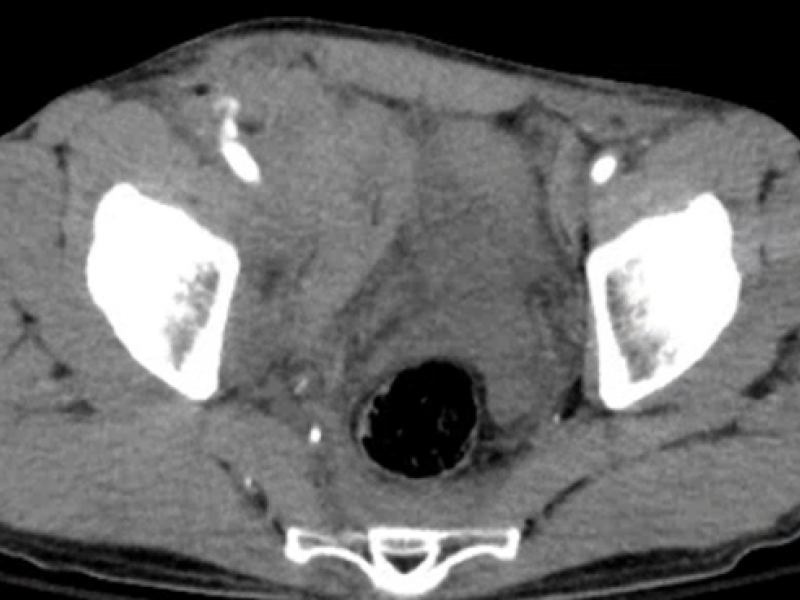

What's the Diagnosis? By Dr. Lauren Murphy

A 58 yo M develops abdominal pain and hypotension 12 hours